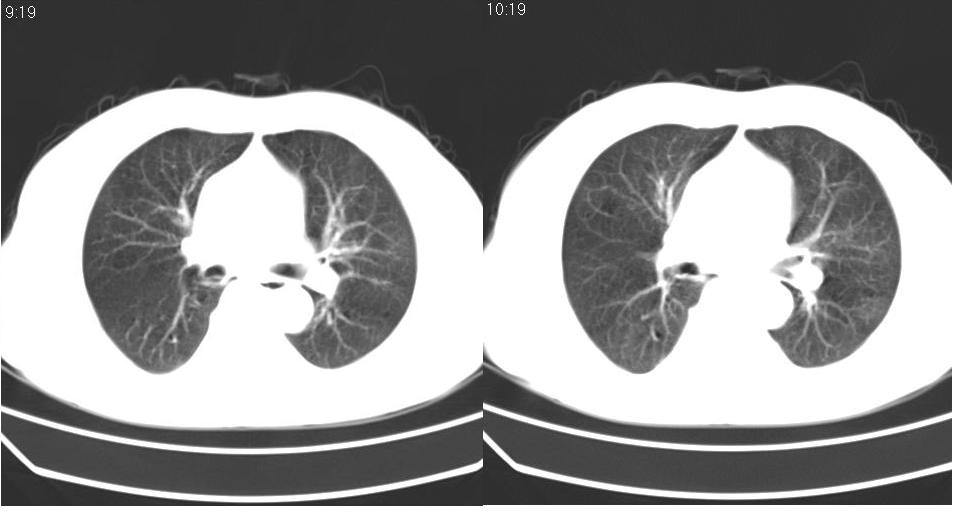

男 60岁,咳嗽,喀痰,胸闷,有吸烟史,正常图片未上传,请谅解。

左肺周围型肺癌。

周围型肺癌

首先考虑:周围型肺癌.